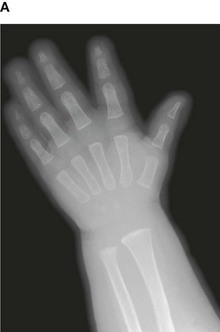

Up until the age of skeletal maturity, bony growth and development follows a typically predictable ordered state, which can be measured through either ultrasound, plain radiographs, or MRI scanning. Typically, the nondominant (left hand) is radiographed and is compared to a series of standard radiographs. From these images the bone age can be determined (Fig. 1.13).

image image image image image

Fig. 1.13 A developmental series of radiographs showing the progressive ossification of carpal (wrist) bones from 3(A) to 10(E) years of age.